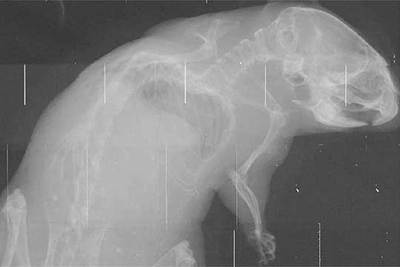

Fernández, implicado directamente en el proyecto, ha asegurado que el nuevo sistema "estará listo en septiembre". A partir de esa fecha la ciencia dejará paso al mercado: "Una empresa debe hacerse cargo entonces del proyecto", afirmó. Con el nuevo sistema han radiografiado a una anchoa, un caracol y un ratón. Las últimas pruebas se harán con tejidos muertos. El proyecto Dear-Mama (Detection of Early Markers in Mammography) ha sido financiado por la UE (1,2 millones de euros) y cuenta con la colaboración de seis instituciones, el IFAE, el Centro Nacional de Microelectrónica, del CSIC, la Sociedad Española de Electromedicina y Calidad, el Hospital Parc Taulí de Sabadell, el Hospital Universitario de Viena y el Hospital Infantil Armand-Trousseau, en Francia.

El nuevo sistema es de "interés capital para la detección temprana de tumores y eficaz para la osteoporosis, que podría detectarse en sus primeras fases dada la calidad de la imagen", afirmó Fernández.